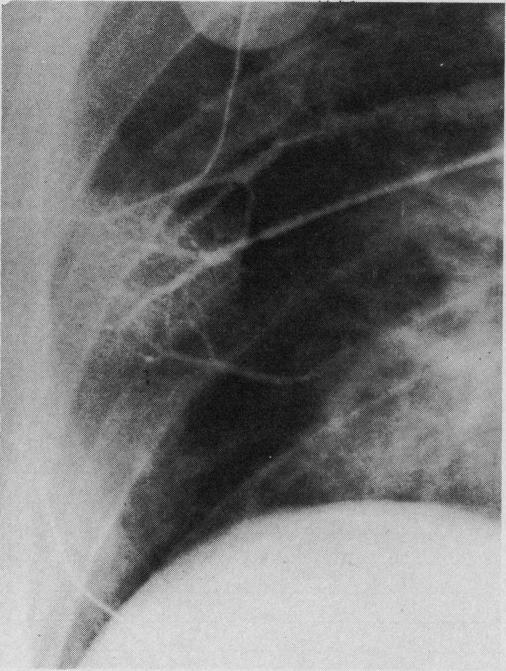

An investigation was conducted to assess the accuracy of left heart filling pressures determined by a right heart catheter introduced at the bedside. Twelve patients were studied after open cardiac surgery by simultaneously recording pressures from both sides of the pulmonary capillary bed with a direct left atrial catheter and a flow-directed pulmonary arterial catheter. The mean pulmonary artery "occluded" pressure was shown to be a highly reliable index of mean left atrial pressure in all cases. It was much more accurate than pulmonary end-diastolic pressure, especially in six patients with pre-existing pulmonary hypertension.